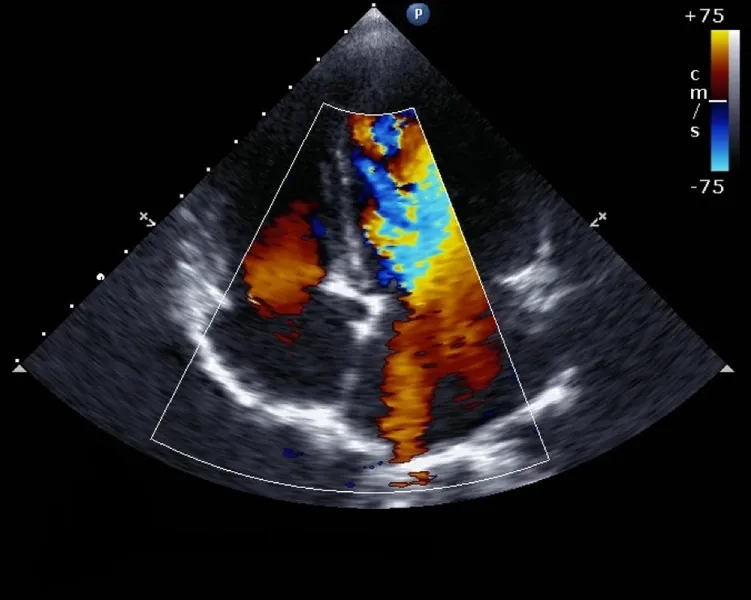

• Siêu âm tim: Đây là phương pháp chính để chẩn đoán bệnh lý hở van 3 lá đồng thời cũng có thể chẩn đoán chính xác mức độ hở van tim và các tổn thương đi kèm.